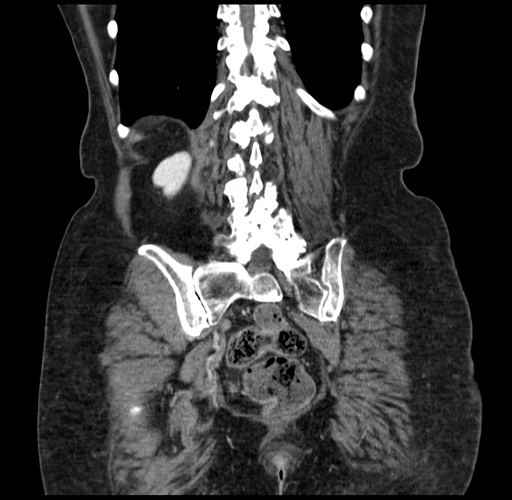

Axial Venous

Coronal Venous